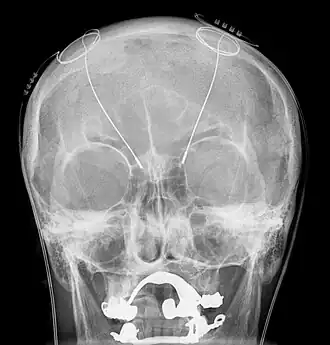

Van tevoren worden de hersenen nauwkeurig in beeld gebracht, bij voorkeur met een MRI-scan. De operatie begint met het aanbrengen van een raamwerk, een “frame” op de schedel. Vervolgens wordt er een CT-scan gemaakt van het hoofd met het frame. Door deze te combineren met de tevoren gemaakte MRI-scan, kan de computer precies berekenen op welke coördinaten de elektroden moeten komen. Tijdens het eerste deel van de operatie, het inbrengen van de elektroden, blijft de patiënt bij kennis. Door een opening die onder plaatselijke verdoving in de schedel wordt gemaakt, wordt de elektrode ingebracht. De elektrode heeft vier afzonderlijke contactpunten, zodat je op verschillende plaatsen in het geïmplanteerde hersengebied kunt stimuleren. Doordat de patiënt bij kennis is, kan door middel van proefstimulatie precies gezien worden wat het effect is en kan de plaatsing eventueel worden bijgesteld. Als de elektroden naar wens geplaatst zijn, wordt de patiënt onder narcose gebracht en kan de rest van de apparatuur worden ingebracht.

De techniek die gebruikt wordt om de elektrode te plaatsen, heet stereotaxie. Tevoren wordt op de millimeter nauwkeurig de gewenste plaats van de elektrode bepaald, waarna deze door een kleine opening in de schedel kan worden ingebracht.